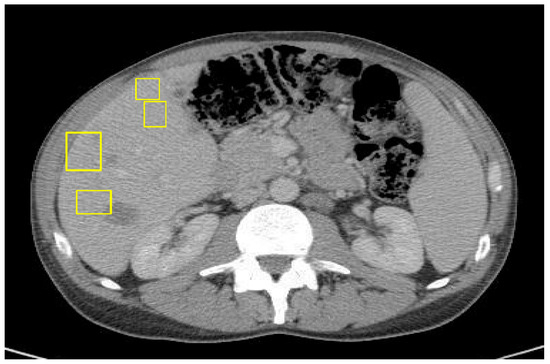

A 45-year-old male with a past medical history of lactose intolerance presented to his primary care physician with a five-week history of right lower-quadrant abdominal pain, bloating, swelling, discomfort, and increased flatulence. On physical examination, a visible and palpable mass was noted in the right lower quadrant. A contrast-enhanced computed tomography (CT) scan of the abdomen and pelvis revealed an 8 cm mass arising from the cecum, accompanied by presumed metastatic mesenteric lymphadenopathy and potential early invasion of the right lower-quadrant anterior abdominal wall musculature (Figure 1).

Figure 1. Mass with dimensions of 8 cm in cecum; presumed metastatic mesenteric lymphadenopathy with possibility of early invasion of RLQ anterior abdominal wall musculature.